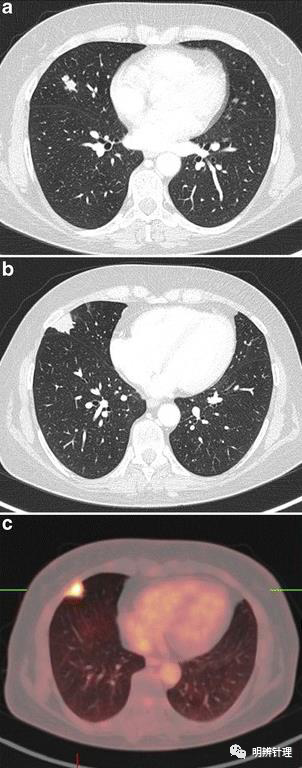

女性,54 岁。既往有小细胞肺癌脑转移病史,在随访期间出现两个肺结节。肺CT 显示右中叶有两个结节:

(a)17 mm 带毛刺和分叶结节在 18F-FDG-PET 上仅显示少量摄取,已发现3年,逐步增大;

(bc)为新发现结节。22 mm 胸膜下带毛刺结节,PET-CT强烈摄取。

(a)典型类癌(b)结核癌